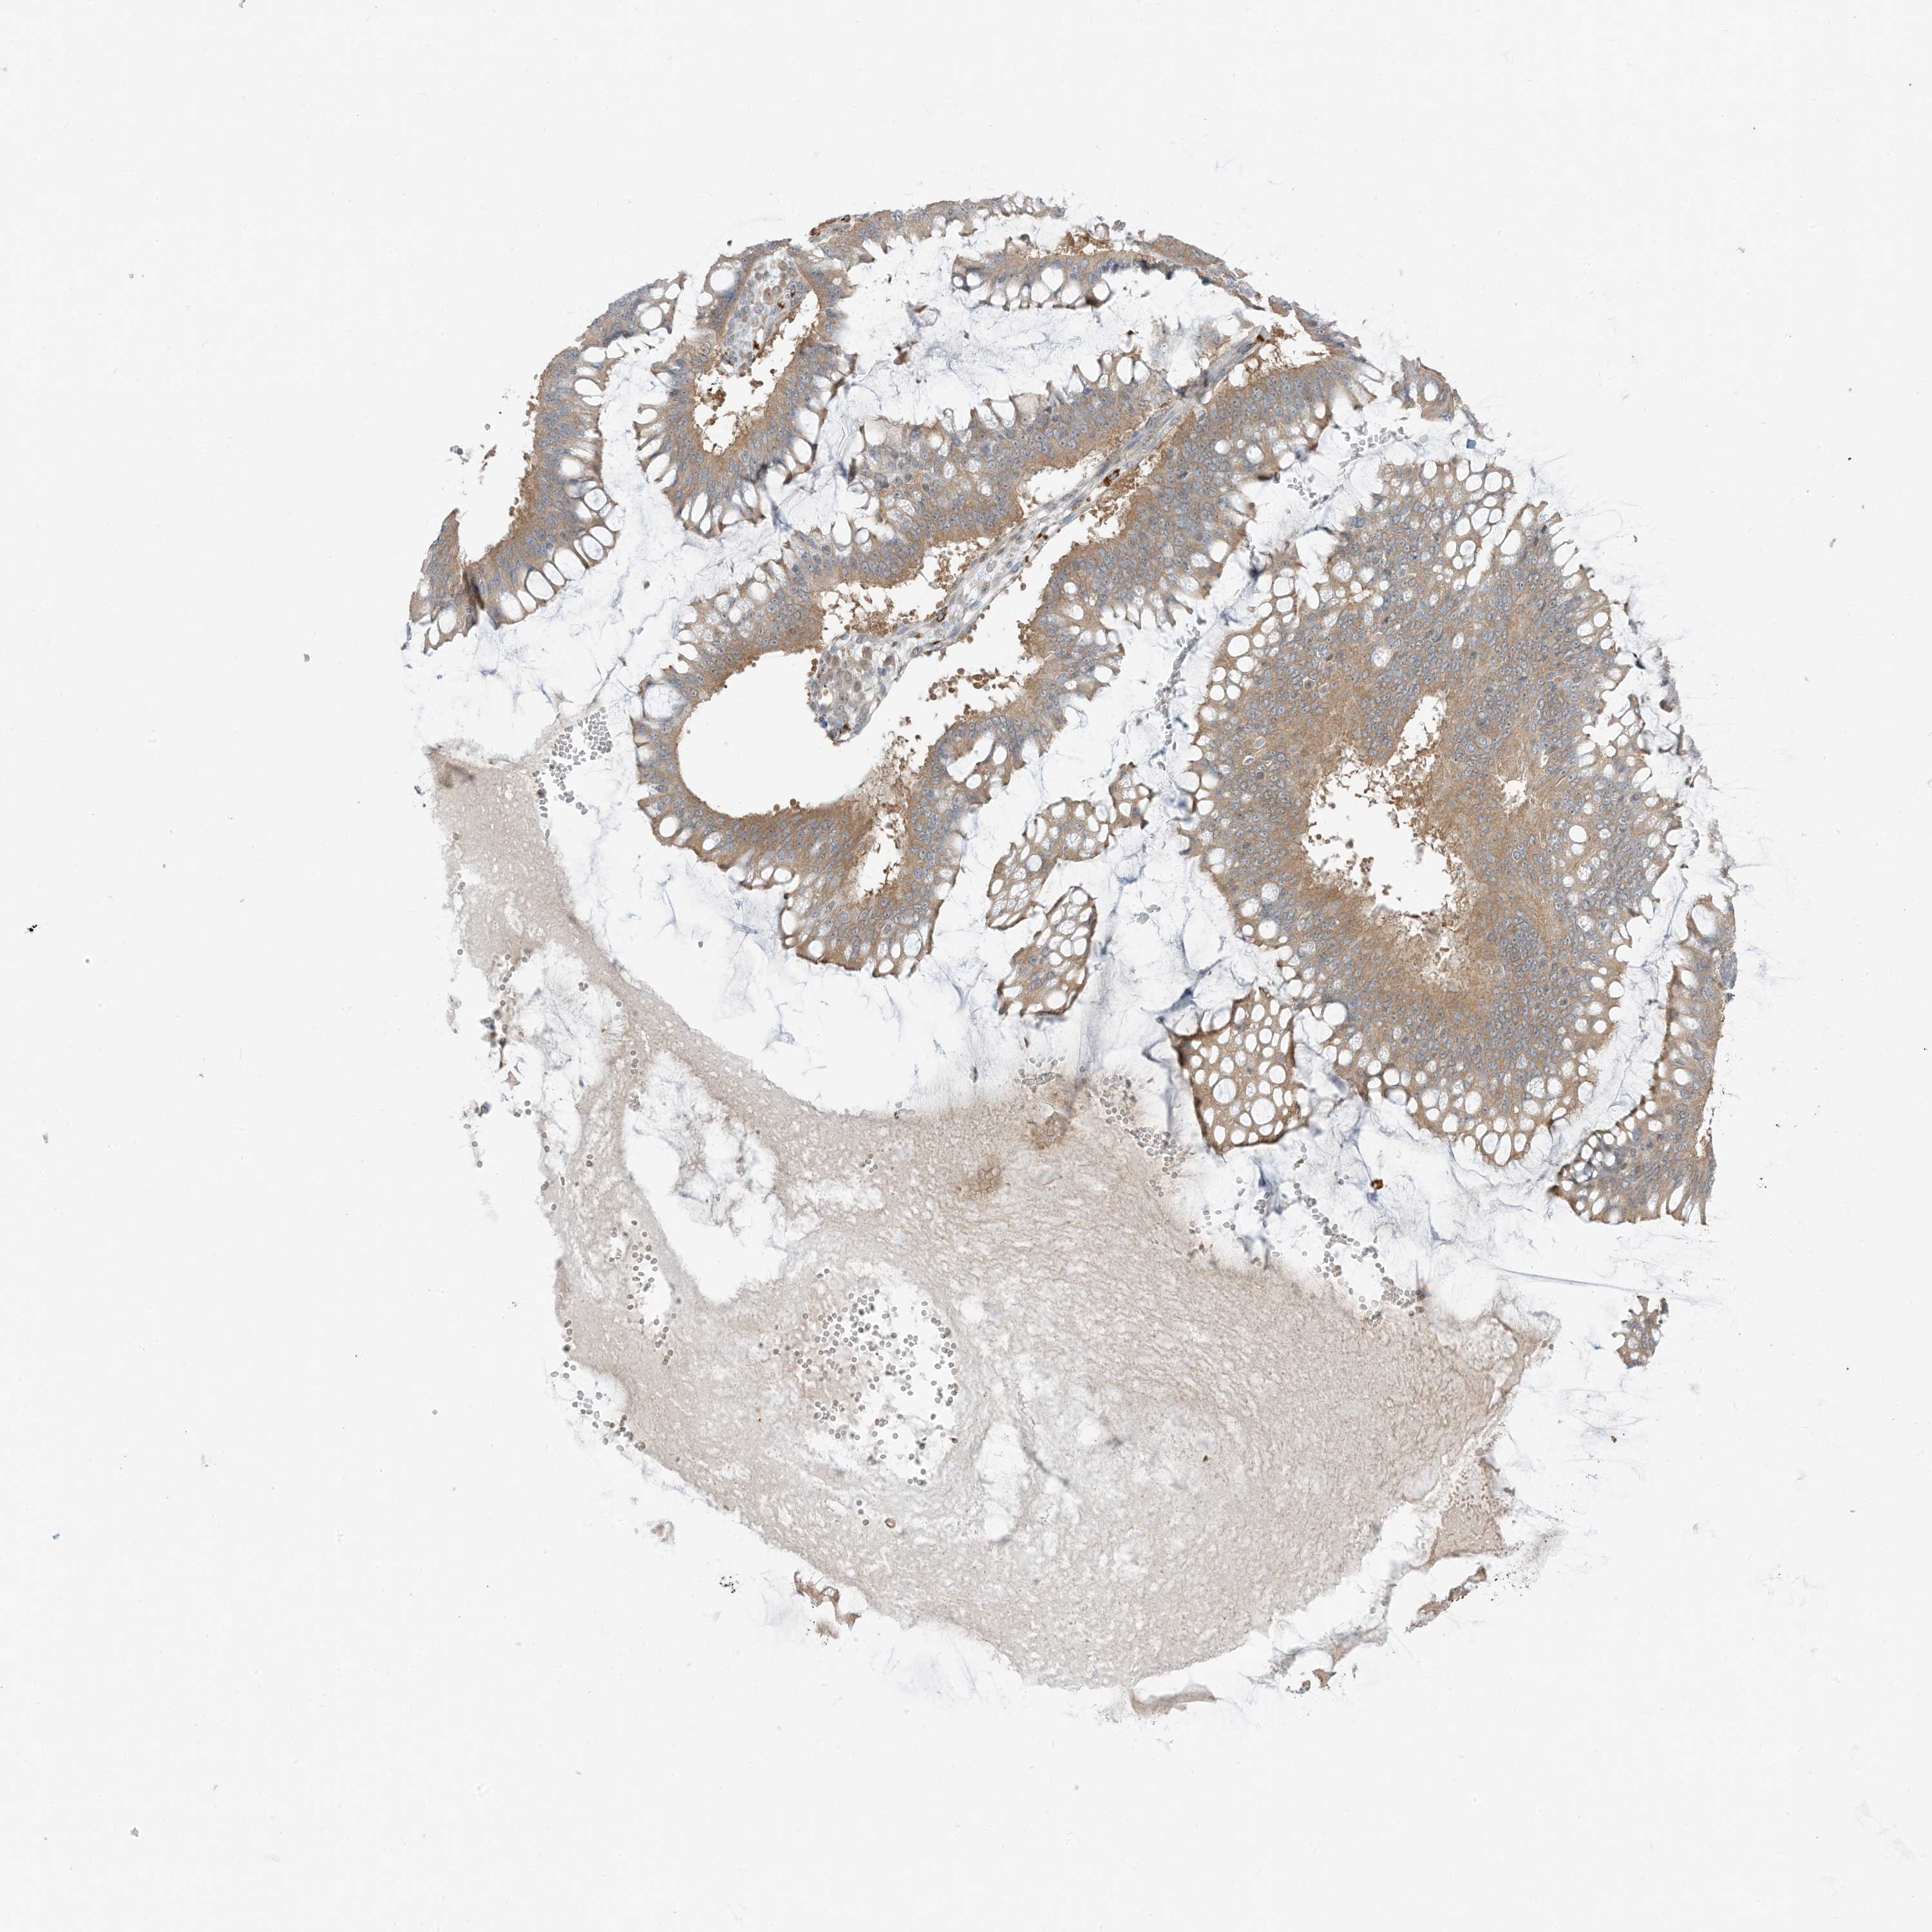

OVARIAN CANCER - Protein expressioni

A mouse-over function shows sample information and annotation data. Click on an image to view it in a full screen mode. Samples can be filtered based on level of antibody staining by selecting one or several of the following categories: high, medium, low and not detected. The assay and annotation is described here.

Note that samples used for immunohistochemistry by the Human Protein Atlas do not correspond to samples in the TCGA dataset.

Antibody stainingi

Antibody staining in the annotated cell types in the current human tissue is reported as not detected, low, medium, or high, based on conventional immunohistochemistry profiling in selected tissues. This score is based on the combination of the staining intensity and fraction of stained cells.

Each image is clickable and will lead to virtual microscopy that enables deeper exploration of all samples and also displays staining intensity scores, fraction scores and subcellular localization as well as patient and tissue information for each sample.

Antibody HPA035491

Staining

High

Medium

Low

Not detected

Intensity

Strong

Moderate

Weak

Negative

Quantity

>75%

75%-25%

<25%

None

Location

Nuclear

Cytoplasmic/membranous

Cytoplasmic/membranous,nuclear

Cystadenocarcinoma, serous, NOS

Carcinoma, endometroid

Cystadenocarcinoma, mucinous, NOS

Carcinoma, NOS